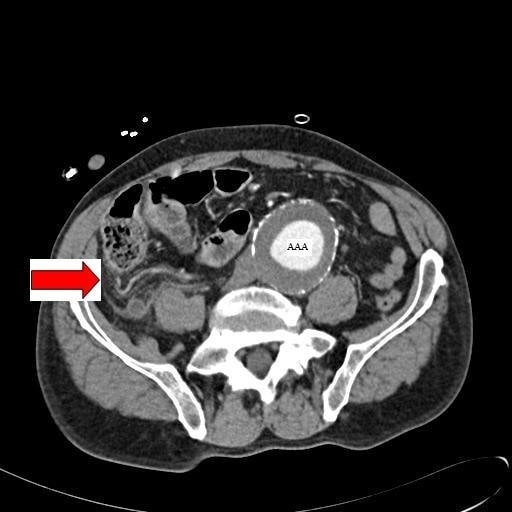

Abdominal CT appendicitis • LITFL • Radiology Library

Abdominal CT appendicitis • LITFL • Radiology Library What Does An Inflamed Appendix Look Like On Ultrasound In a constant position, usually at the. • primary us for aa diagnosis will decrease. • ultrasound (us) should be the first imaging modality for diagnosing acute appendicitis (aa). Assuming that non visualization of the appendix means that the appendix is normal. What does appendicitis look like? It is often associated with surrounding “creeping fat”, which is the. The appendix. What Does An Inflamed Appendix Look Like On Ultrasound.